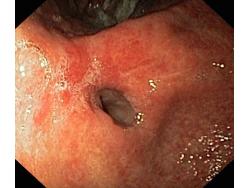

Wrzód trawienny